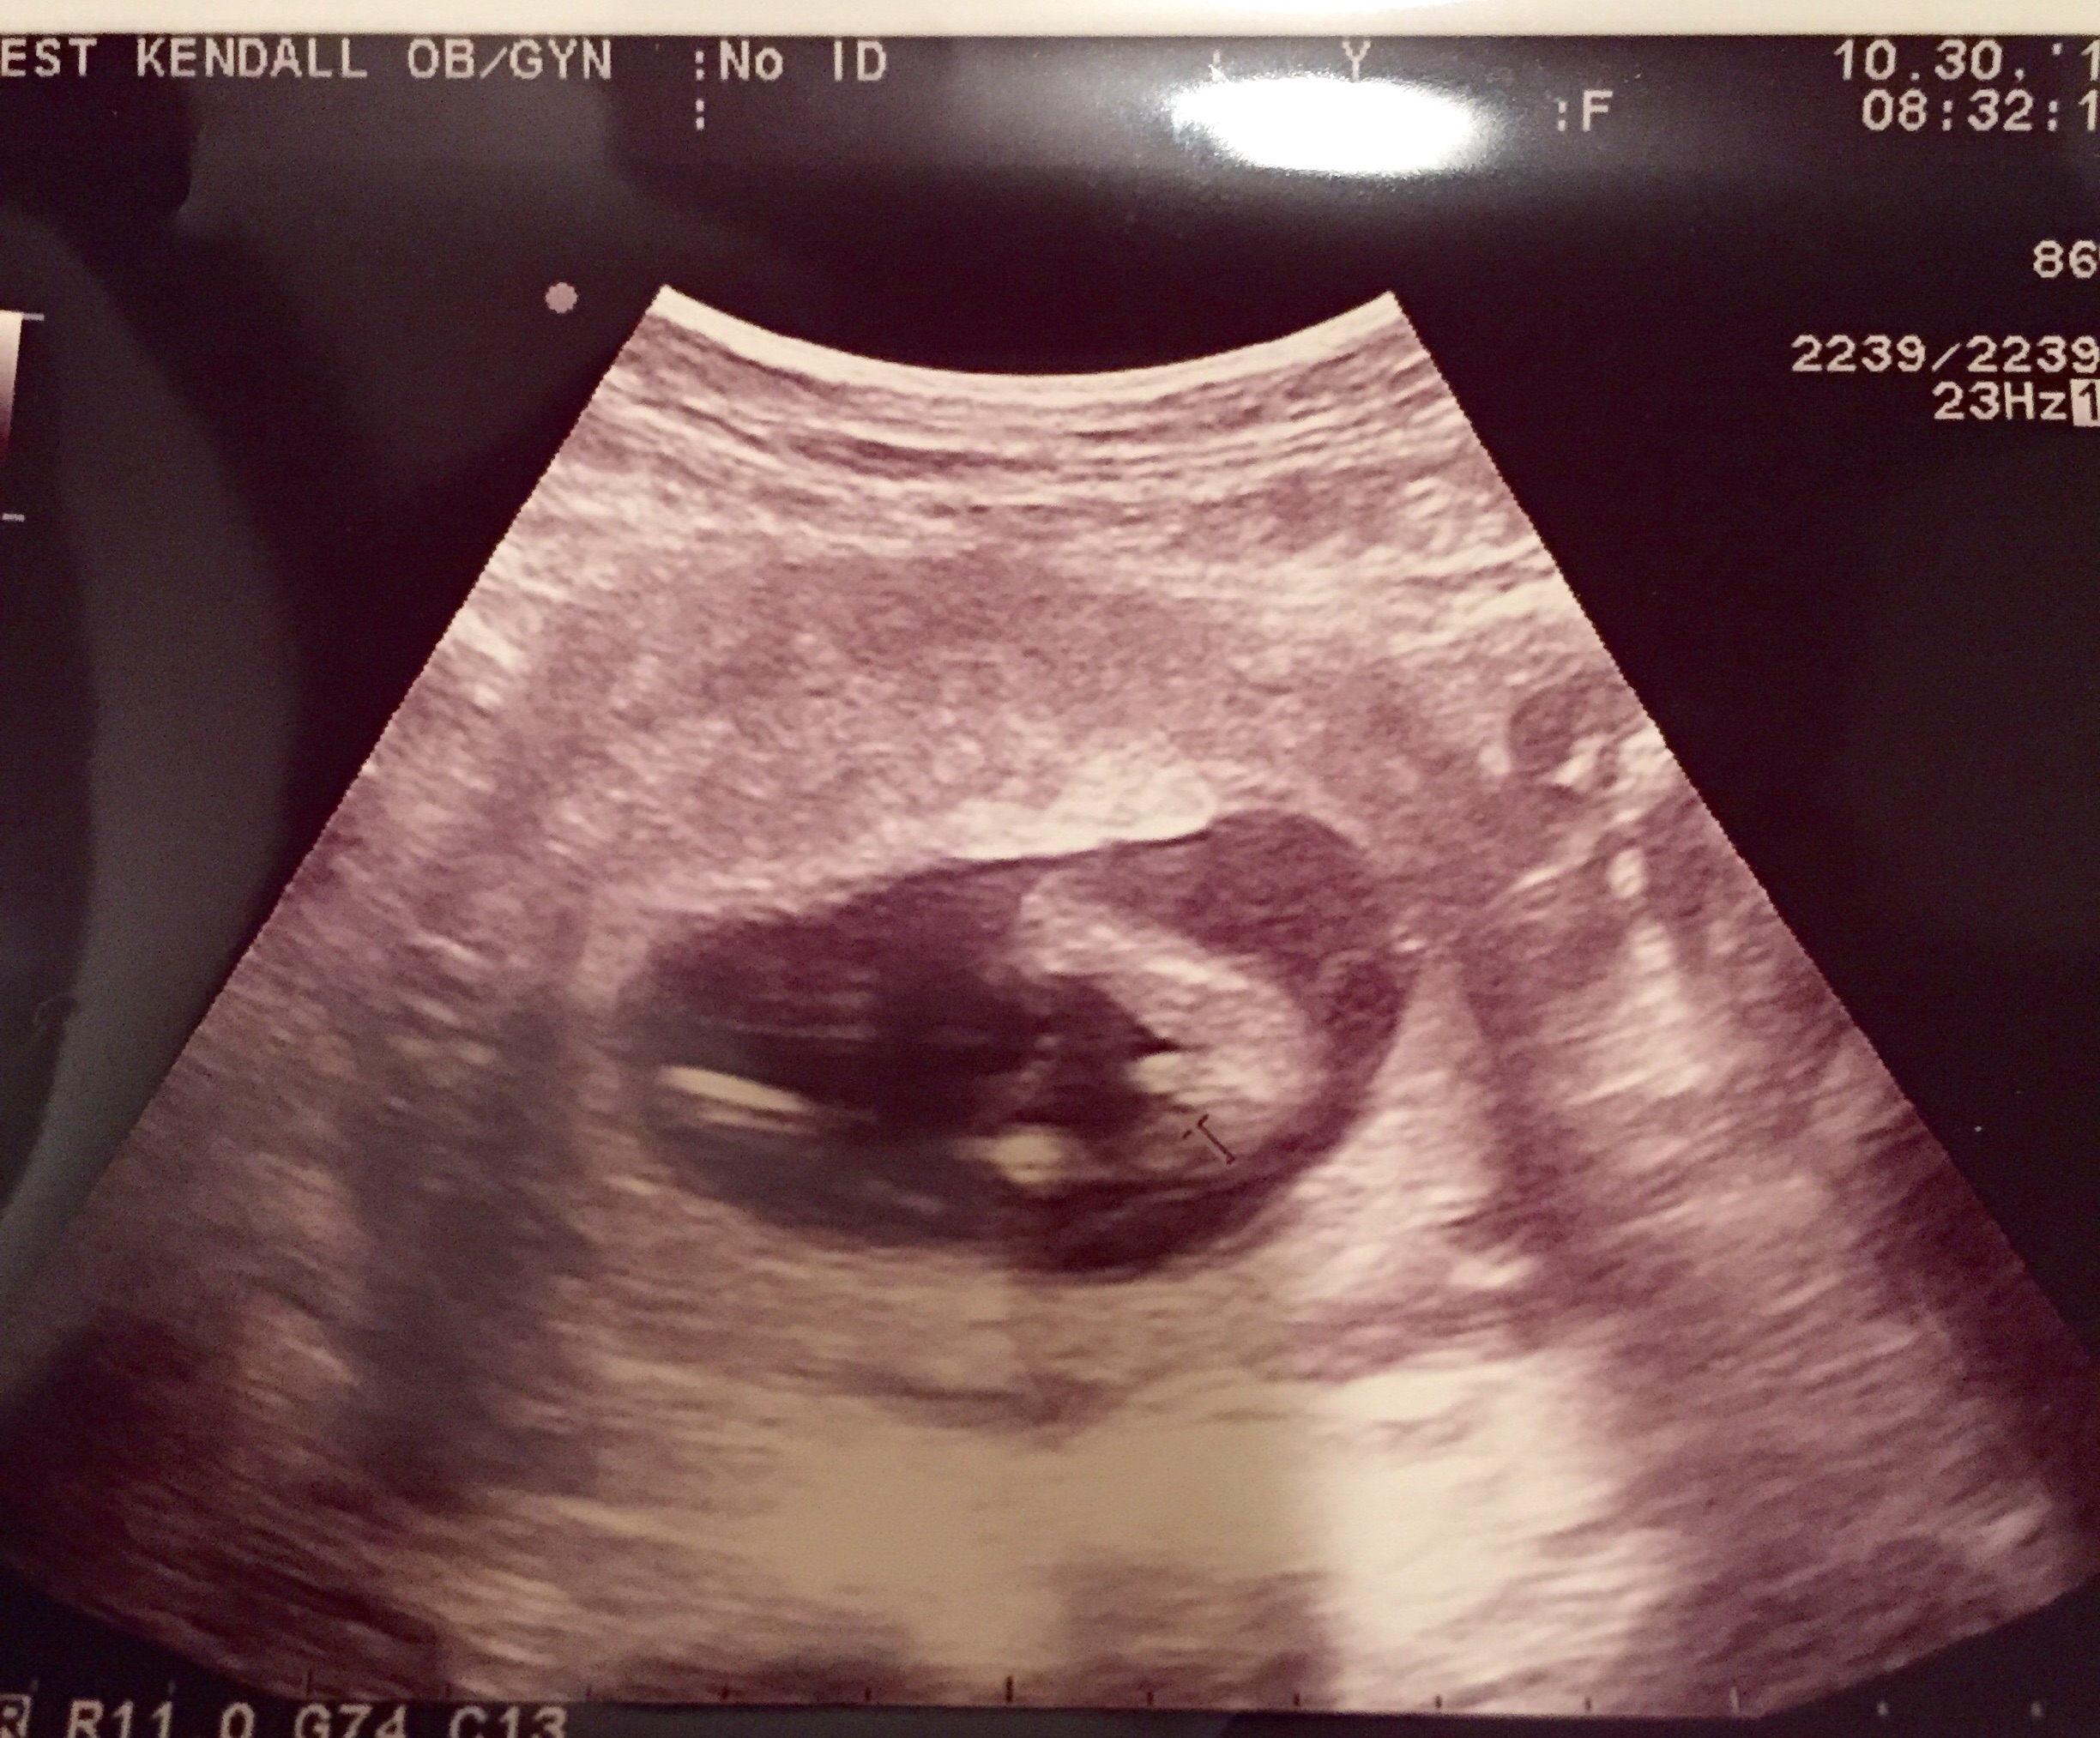

Hello ladies I need some opinions. I went in for my 12 week appointment and at my office they do an ultrasound every visit to hear the heartbeat and while the tech was doing that she took a little longer and showed between the baby's legs and told me I was expecting a boy. Should I trust her answer so early on? Thanks!

@Pintobean39 I was used as a test dumby for some radiology students. They said it starts too form as early of 12-13 weeks but it's not really genatalia. It's two lines vs three lines.

Genitalia is the same up until week 9. Between I wanna say 5-12 is when testosterone is turned on creating male genatalia. In the absence of androgens female genitalia for